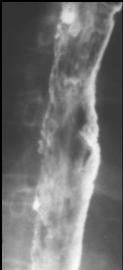

Image de TOGD et double de

contrast transit oesophagien avec aspect crenele de

paroie de oesophage + image des ulceres stagnant de

baryte |

Aspect

crenele de paroie de oesophage avec image des

ulceres etendue alonge l'oesophage |